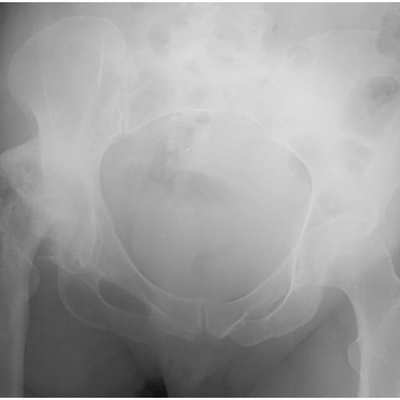

Click on an image below to view more info.